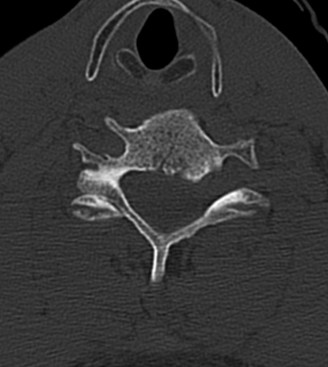

CASE 1 A 63-year-old male sustained a hyperextension injury to his neck while diving into a pool. Upon presentation, he reports decreased sensation in his hands and decreased strength in his arms and wrists, but no lower extremity complaints. On motor examination, he has 5/5 strength in his deltoids and elbow flexors and 4/5 strength in the elbow extensors, wrist extensors, and finger flexors. Lower extremity motor examination is normal. Sensation is decreased to light touch in both hands. Otherwise his sensation is preserved. Images of his cervical spine are shown in Figures 1–1 to 1–3.

Figure 1–3

The correct answer is (B). The clinical scenario describes a patient with central cord syndrome (CCS). CCS continues to be the most common incomplete spinal cord injury accounting for 15.7% to 25% of all spinal cord injuries. The characteristic presentation is an extension moment injury in a previously spondylotic and stenotic spine. Figures 1–1 to 1–3 demonstrate a spondylotic spine with central narrowing and CSF effacement that is worst at the C3–4 level. Bleeding, edema, and/or Wallerian degeneration lead to damage of the lateral corticospinal tract which is the main descending motor tract in the spinal cord. The more central anatomic position of the homunculus to the upper extremities places them at greater risk than those to the lower extremities. As such, injury to the lateral corticospinal tract is characterized by upper more than lower extremity involvement and motor deficits being more pronounced than sensory deficits.